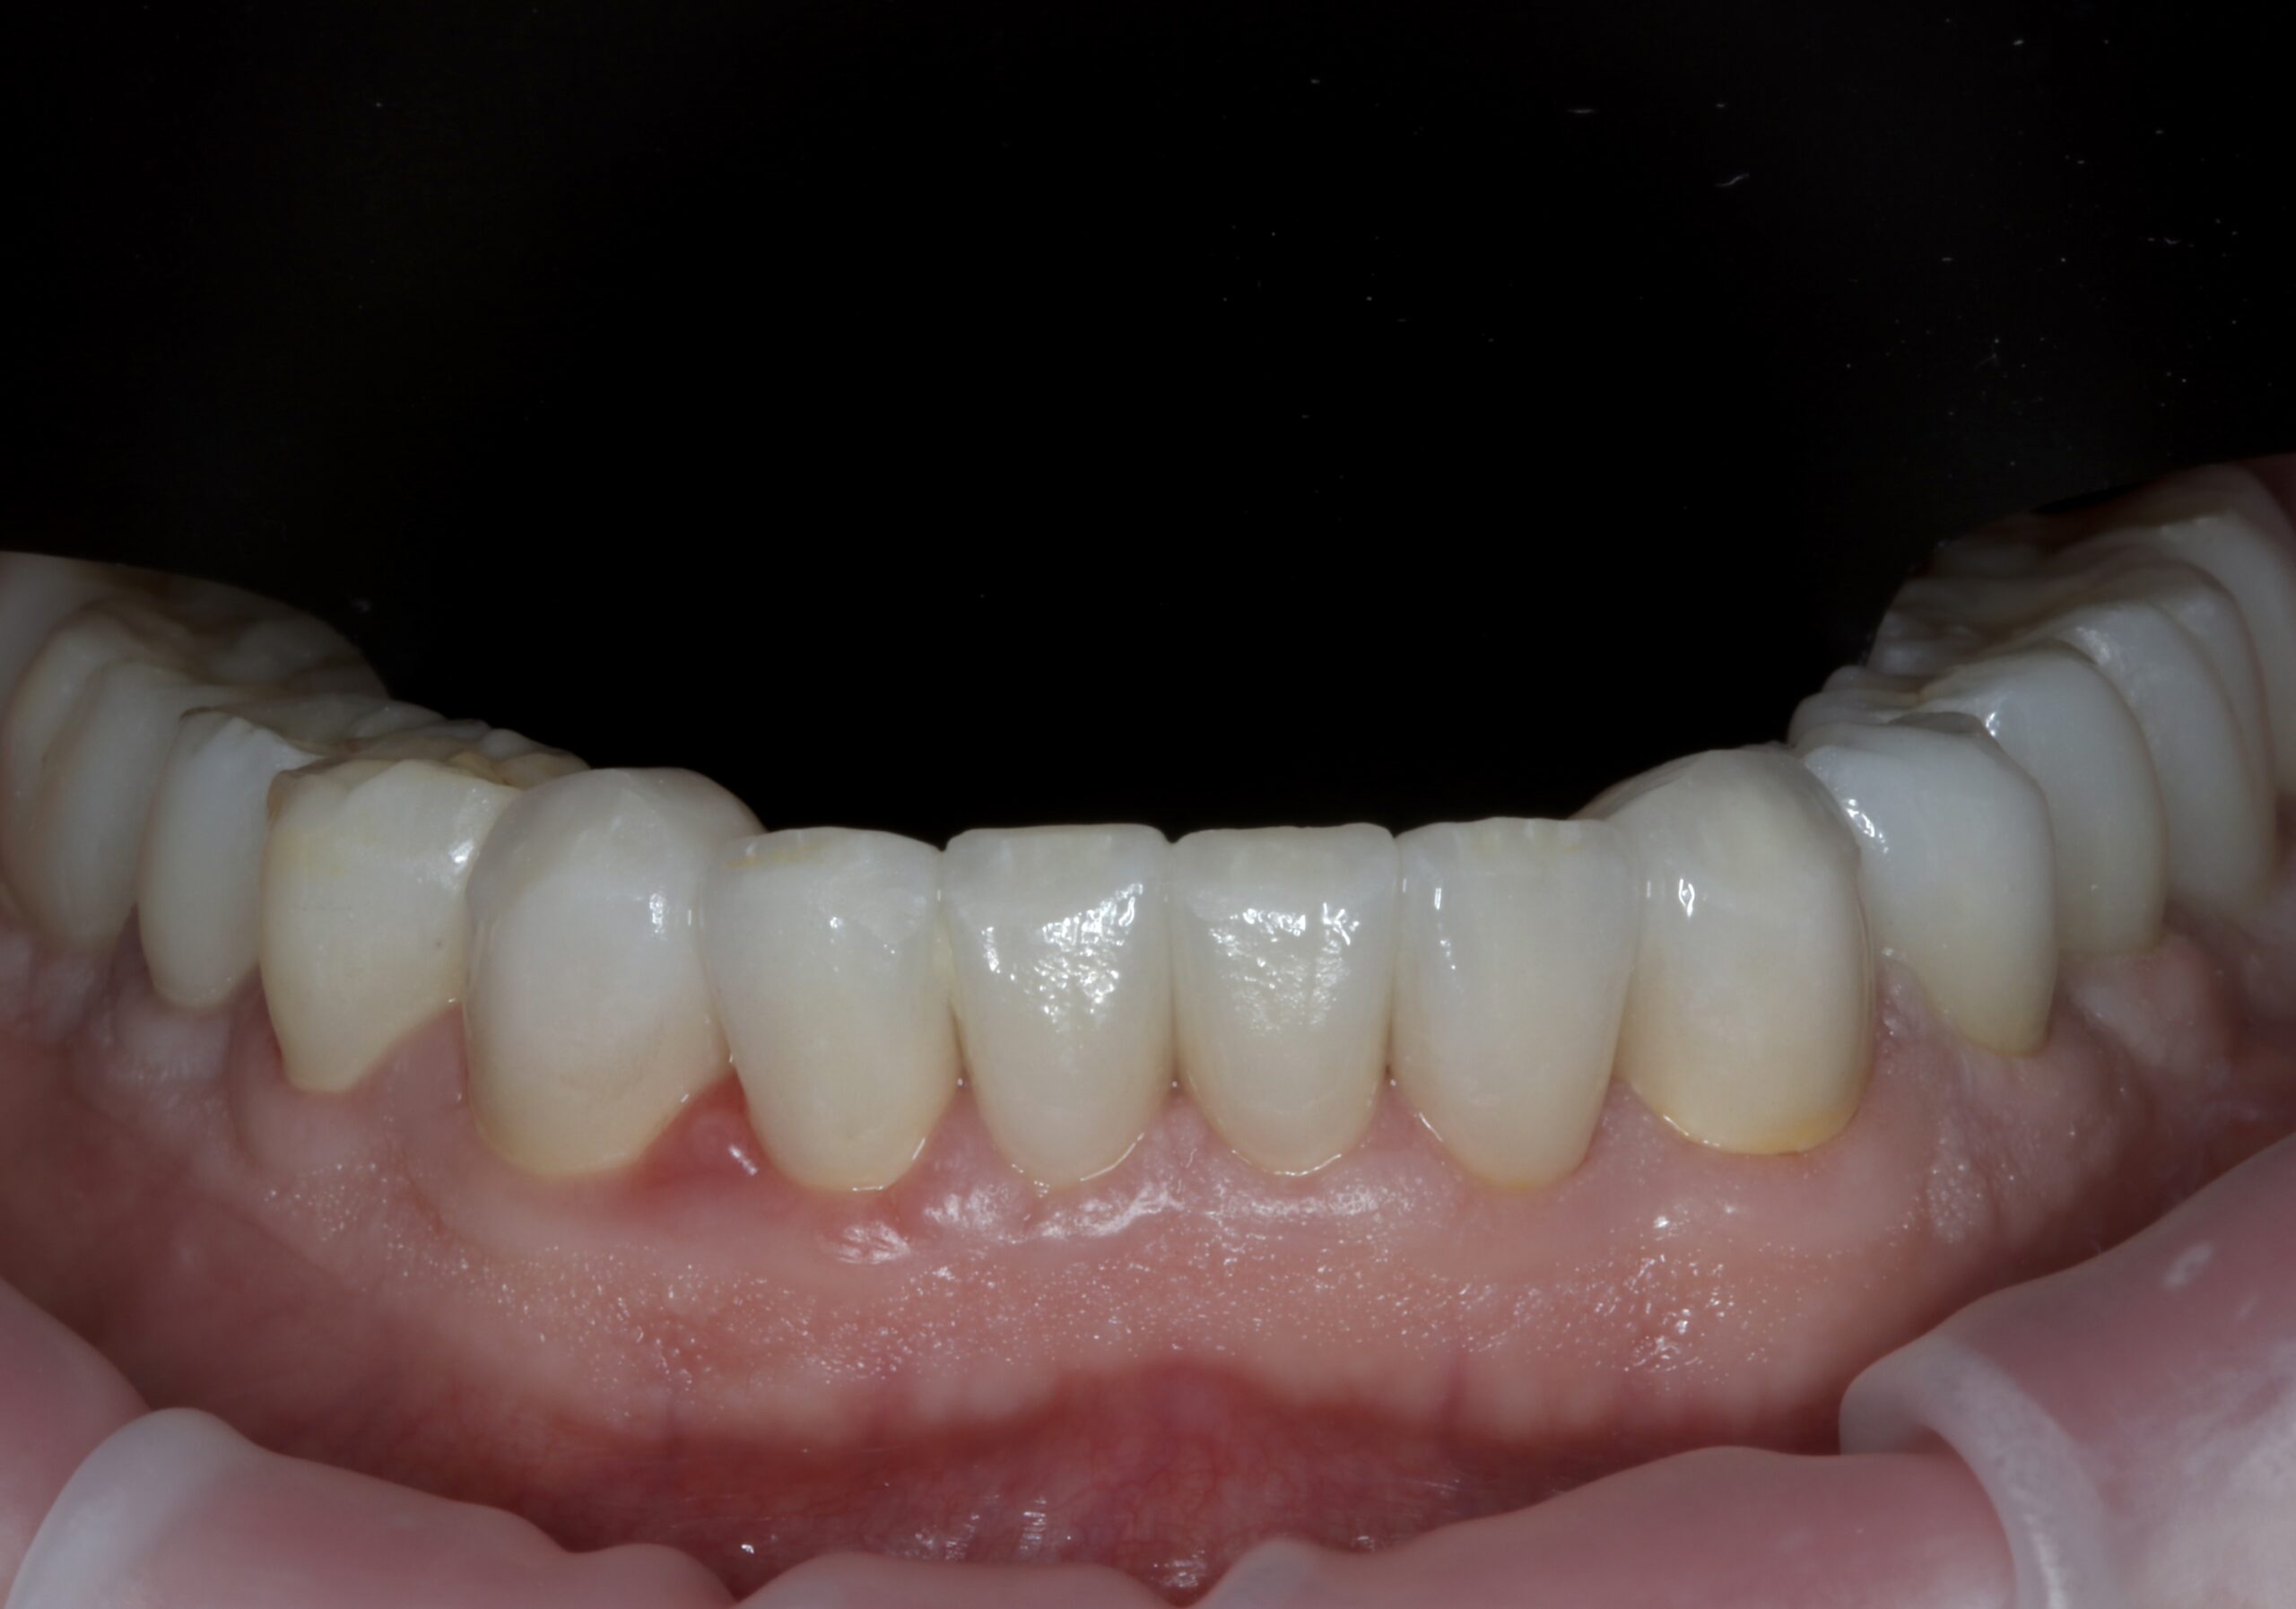

Cas 3

Dr Eyal Assaraf Réhabilitation d’un cas d’érosion dentaire